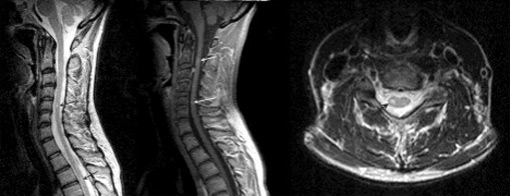

Зачем перед МРТ пить Но-шпу? Отвечает Черкасова С .А .: врач-рентгенолог высшей категории За 40 минут до исследования МРТ органов, при отсутствии индивидуальной непереносимости, необходимо принять антиперистальтическое средство «Но-шпа» в дозе 80-120 мг (2-3 таб) .

Магнитно-резонансная томография (МРТ) в большинстве случаев не требует специальной подготовки, однако в некоторых случаях врач рекомендует принять перед исследованием но-шпу .

За три часа нужно принять таблетки «Но-шпа» для снятия спазмов гладкой мускулатуры . Накануне вечером рекомендуется сделать клизму для очищения кишечника . МРТ проводят на голодный желудок, за 2-3 часа стоит воздержаться от употребления жидкости .

Подготовка к МРТ мочевыделительной (мочеполовой) системы . Наполненный мочевой пузырь - пить перед исследованием (500-700мл) не мочиться 1 час . Не есть за 3 часа до исследования (если предполагается внутривенное контрастирование) . Лекарства принимать можно . За 6-8 часов 2 таблетки НО-ШПА Форте + За 30 минут до исследования 2 таблетки НО-ШПА .

За 30-40 минут до начала исследования - прием 1-2 таблеток «Но-шпа» . Не мочиться за 2 часа до проведения исследования . Дополнительный прием жидкости не нужен - мочевой пузырь должен быть умеренного наполнения . Подготовка к исследованию КТ малого таза Купить одну ампулу «Урографин» 20 мл («Вирографин») любой процентности (60-76%)

- за 30-40 минут до процедуры нужно принять препарат, препятствующий повышенной перистальтике кишечника (бускопан, но-шпа, дротаверин 120мг), или перед исследованием внутримышечно или внутривенно 1мл глюкагона . Особенности подготовки к МРТ брюшной полости, МРТ малого таза, МРТ всего тела для женщин